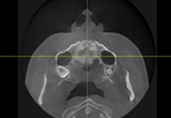

Полная проверка состояния носа благодаря снимкам КТ.

Благодаря 3Д-КТ снимкам возможно рассмотреть в мельчайших подробностях не только состояние костей носа, но и форму, состояние и размеры мягких тканей вокруг него, что позволяет правильно составить безопасный план операции.

Из за большой нижней носовой раковины возможно появление заложенности носа, такие проблемы также возможно одновременно устранить во время пластической операции.

За счет точного определения размера и формы костей, во время ринопластики по коррекции ширины носа возможно одновременно провести остеотомию носа.